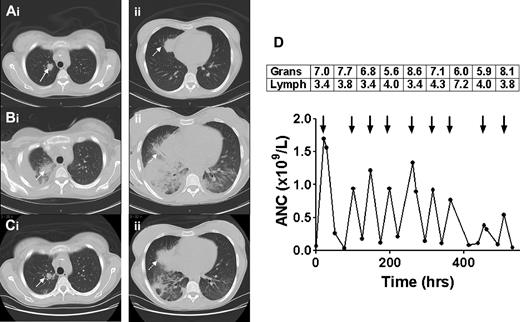

Sequential CT scans of the thorax and response to granulocyte transfusions. CT scan before granulocyte transfusions showed nodules in the right upper lobe (Ai, solid arrow, 2 cm) and right middle lobe (Aii, dotted arrow, 3.5 cm). CT after 4 transfusions of granulocytes revealed a new right pleural effusion, new right lower and middle lobe consolidation, and left lower lobe airspace disease, and enlargement of existing nodules (Bi-ii). CT after 5 additional granulocyte transfusions showed marked improvement in lung consolidations, accompanied by clinical resolution of fever, tachypnea, and hypoxia (Ci-ii). The granulocyte (× 1010) and lymphocyte (× 109) content of each of the 9 transfused granulocyte components (arrows) is shown in the boxes above the arrows, with the corresponding increment in ANC shown below the arrows (D). Mean granulocyte content was 6.9 × 1010 cells per product.

Unrelated community blood donors were stimulated with dexamethasone 8 mg orally and G-CSF 480 μg subcutaneously, and 12 hours later granulocytes were harvested by hetastarch-assisted leukapheresis.1 Granulocyte components were irradiated and transfused in the afternoon of the same day as collection. A total of 9 components were given on an alternate-day schedule over 3 weeks. CT of the chest after 4 transfusions, at a time of increasing dyspnea and hypoxia, revealed increasing size of existing nodules, and new right lower and middle lobe consolidation and left lower lobe airspace disease (Figure 1B). After 5 additional granulocyte doses, the patient became afebrile, her tachypnea resolved, and the lung nodules and consolidations improved substantially (Figure 1C).

Fever frequently accompanies the administration of granulocyte concentrates and may be seen in 17.5% of transfusions.6 Pulmonary reactions may also occur, presenting as decreased oxygen saturation or as worsening of preexisting infiltrates, as was observed in our case.8 The decision to continue the transfusions after a pulmonary deterioration can be a difficult one. Worsening infiltrates may reflect the trafficking of transfused cells to sites of infection, with activation and release of microbicidal mediators, and may presage subsequent improvement. This appeared to be the case in our patient, as continued transfusions were followed by clinical and radiologic evidence of improvement.